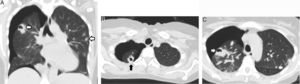

Se presenta el caso de una mujer de 41 años con antecedentes de trasplante renal que había evolucionado a disfunción crónica del injerto, y se encontraba bajo hemodiálisis trisemanal a través de un catéter transitorio yugular. La paciente estaba ingresada con diagnóstico de sepsis por catéter con hemocultivos positivos para Staphylococcus aureus resistente a meticilina. Evolucionó con disnea súbita y dolor torácico a las 72h del ingreso. Se realizó una tomografía computarizada torácica que evidenció un neumotórax derecho asociado a nódulos pulmonares cavitados (fig. 1), algunos de ellos periféricos. Se estableció el diagnóstico de neumotórax espontáneo secundario a la rotura de émbolos sépticos cavitados en el espacio pleural. El neumotórax fue tratado con un drenaje pleural durante 4 días. Se indicó tratamiento antibiótico con vancomicina durante 4 semanas con buena evolución clínica.

La infección asociada a catéter es una causa frecuente de embolias sépticas pulmonares1. El microorganismo responsable suele ser el Staphylococcus aureus. Las lesiones son cavitadas en el 56% de los casos1 y, cuando su ubicación es periférica, pueden abrirse al espacio pleural y desencadenar un neumotórax espontáneo secundario2. Esta complicación es infrecuente y se presenta habitualmente entre los 5 y 15 días de iniciado el tratamiento antibiótico2.